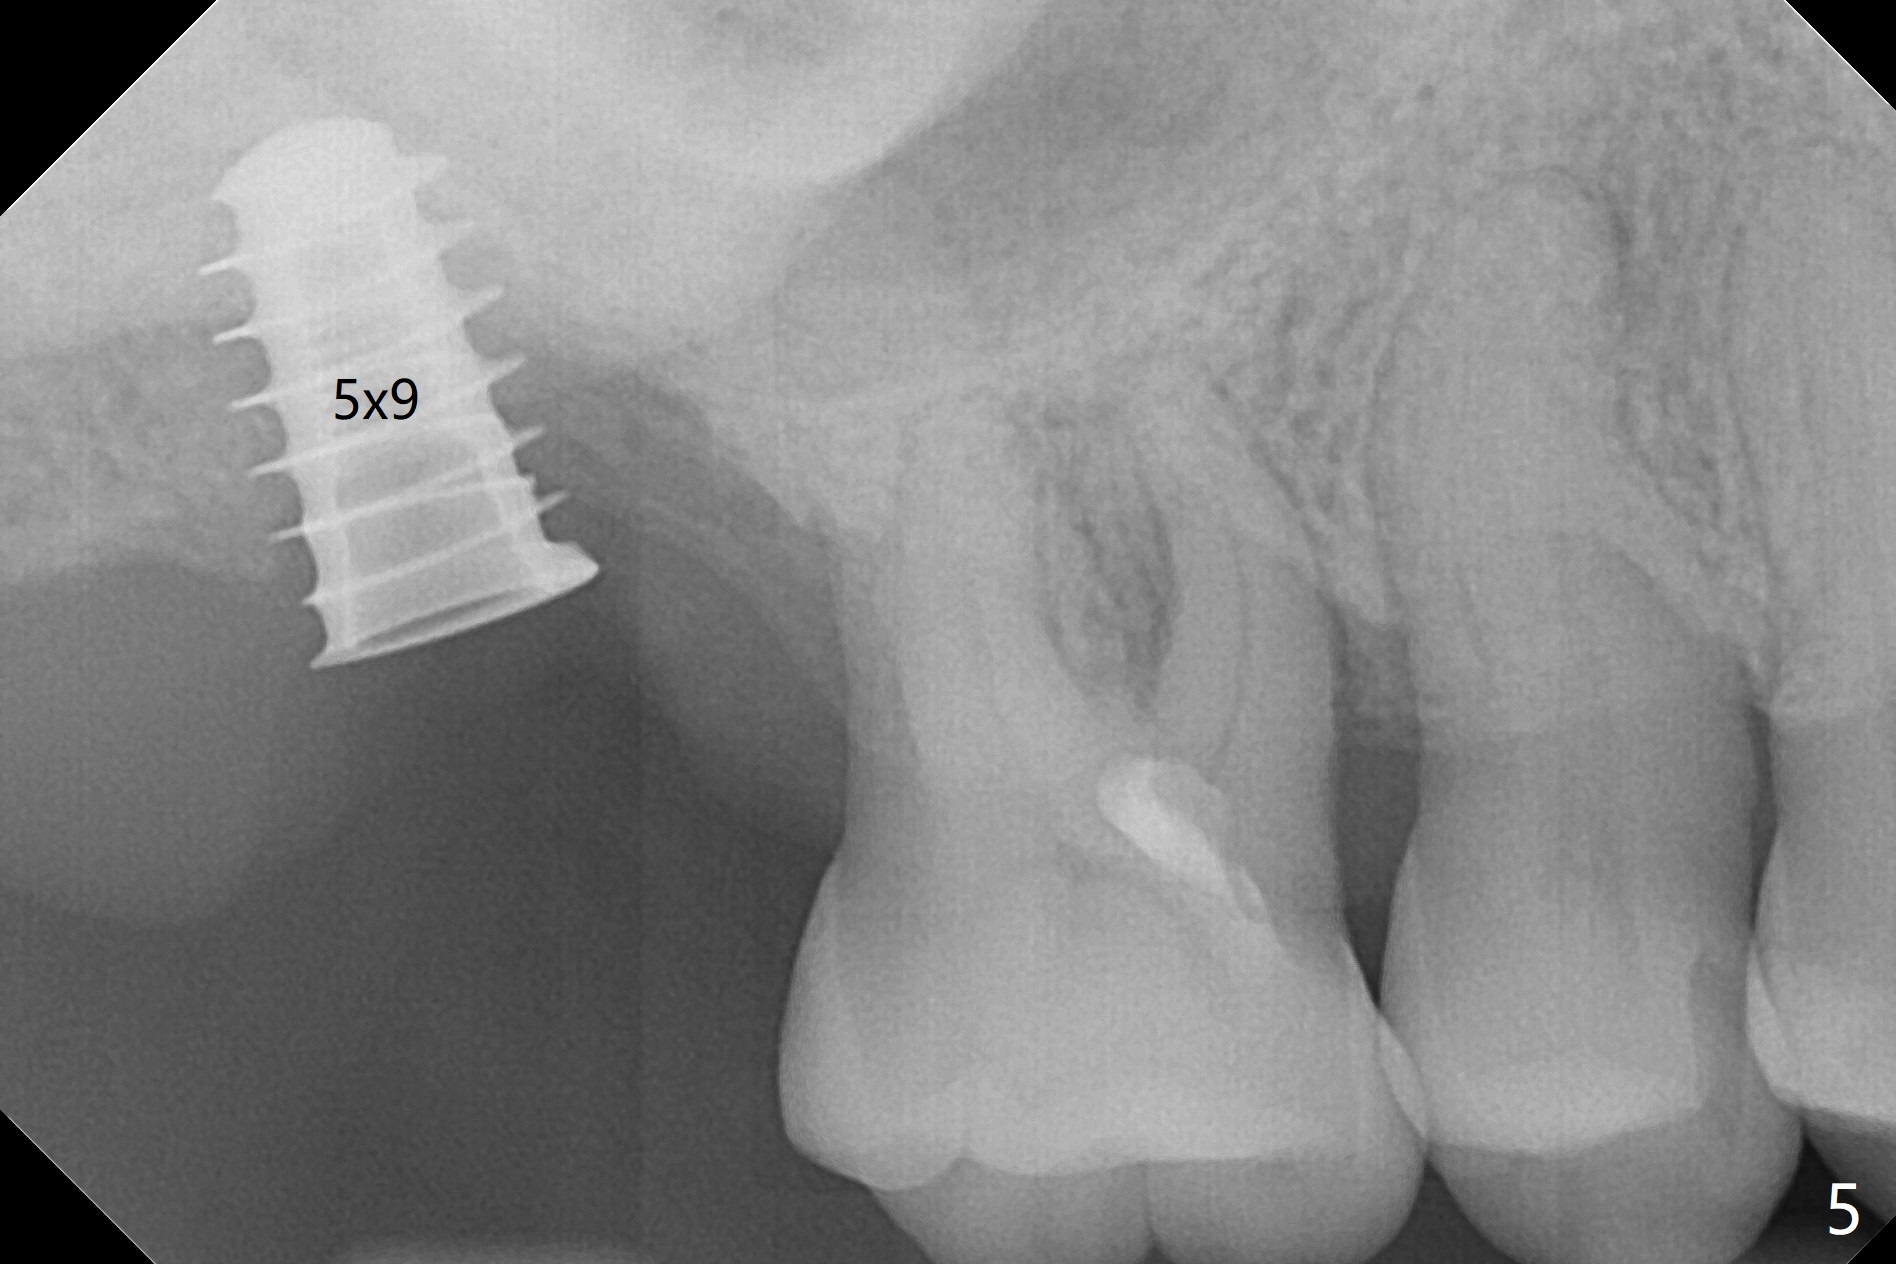

After extraction of the tooth #2 (Fig.1), osteotomy is supposed to be initiated in the mesial slope (Fig.2 arrow). With Magic Expanders (3-4.8 mm), osteotomy ends up in the bottom of the socket (Fig.3). Trajectory is found to be off when 4x9 and 5x9 mm dummy FC implants are placed with stability (Fig.4,5). The final implant, Magicore (5x7(3)mm, >29 Ncm), appears to be placed too deep for restoration (Fig.6,7); a screw retained crown may be a solution. PRF membrane and Vanilla (allograft) are used for sinus lift (no sinus membrane perforation). Following Vanilla graft in the socket gap (Fig.6 *), another piece of PRF membrane is used to cover socket opening. The membrane is fixed in place with suture and periodontal dressing. The implant seems to have osteointegrated 3.5 months postop (Fig.8). After change to 4.3x5 mm solid abutment and mesial surface adjustment, impression is taken for early loading because of removal of #14 implant. In fact the patient is satisfied with mastication improvement at #2 later on.